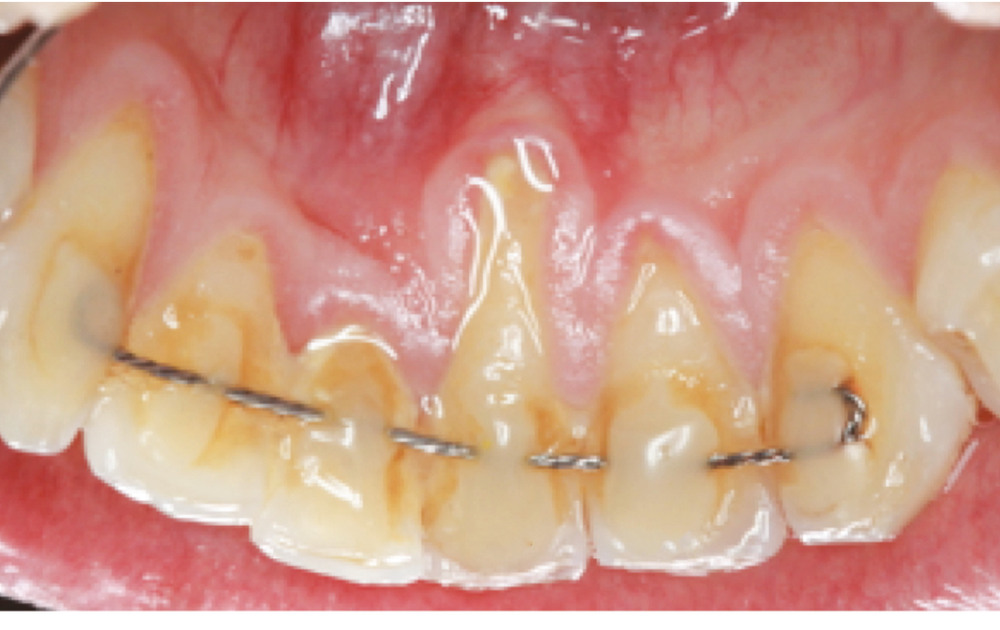

Cependant, dans certains cas, des déplacements dentaires inexpliqués sont observés, sans fracture du fil ou de la colle, provoquant des espaces entre les incisives, des modifications de torque (ou inclinaison vestibulo-linguale) au niveau des incisives maxillaires, des modifications de torque opposées entre deux incisives centrales mandibulaires ou « X effect » (fig. 1 et 2) ou des inclinaisons opposées des canines mandibulaires contro-­latérales (linguale pour l’une, vestibulaire pour l’une) ou « Twist effect » [4] (fig. 3 et 4). Ces mouvements n’apparaissent pas immédiatement après la pose de la contention, mais dans les 5 ans qui suivent.

Renkema et al. [2] et Katsaros et al. [5] estiment que 2,7 à 5 % des patients ayant des fils collés flexibles ont des modifications inexpliquées post-traitement. Il peut alors y avoir nécessité de reprendre le traitement orthodontique et, dans certaines situations, les fortes inclinaisons des dents peuvent entraîner des complications parodontales telles que des récessions…